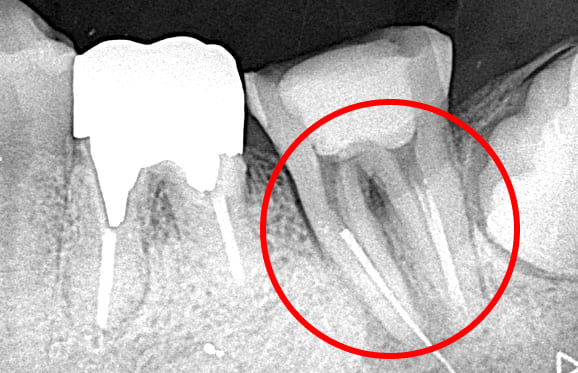

01 右上の頬側根に手用ファイルの破折

02 ファイル除去時

※若干の打診痛あり

03 最終の根充剤を充填